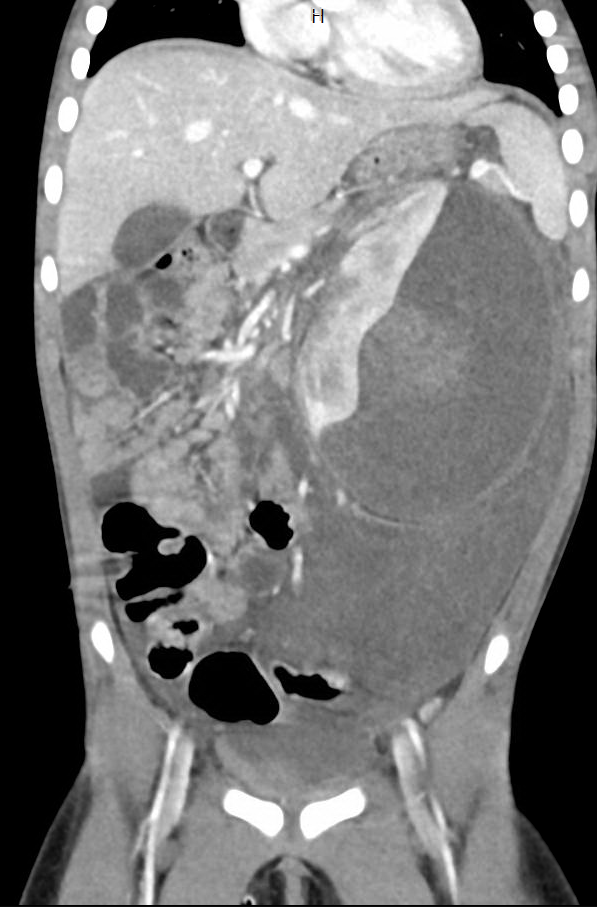

Renal Trauma

Renal trauma accounts for approximately 1-5% of all trauma admissions and as many as 10% of patients who sustain abdominal trauma. Injuries can range from contusions to life threatening injury. The types of trauma include penetrating (gsw, knife), blunt force (mva, sports injury), post procedure etc..

Patients may have abdominal/flank pain on the affected side, hematuria may also be present.